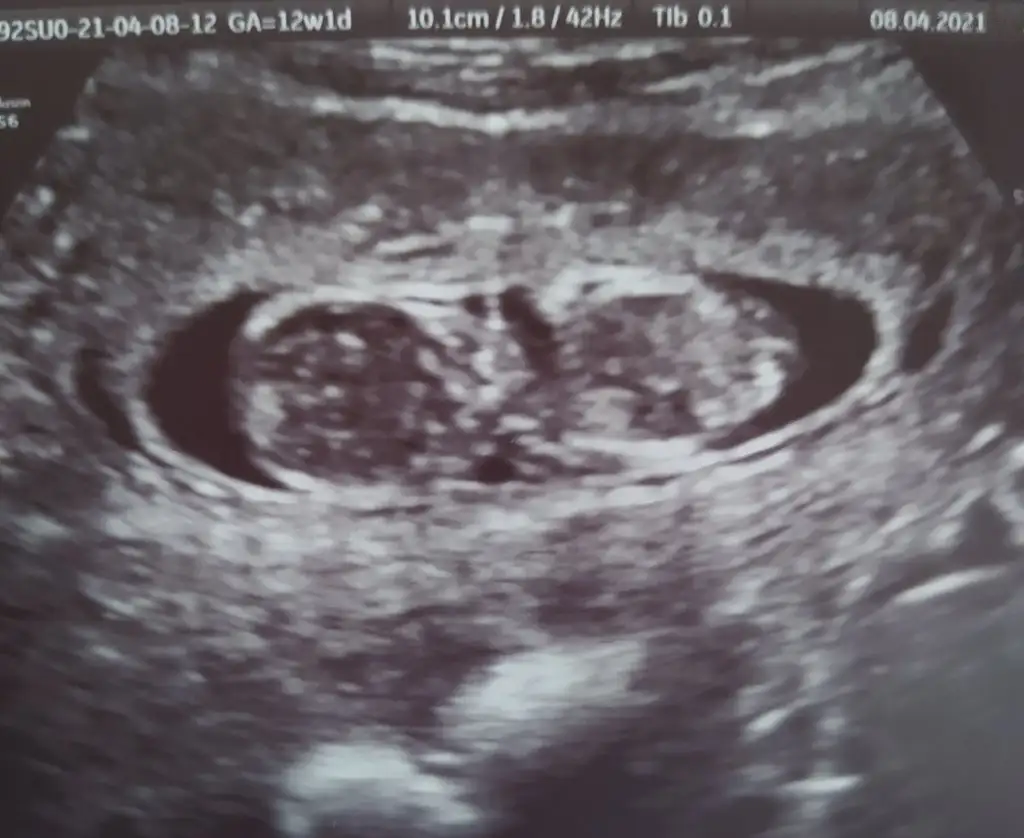

dr soylemeden siz gorun genital nub teorisi ( bebegin cinsiyeti)

Ikra meyra Ikra meyra canim 12+2 bı tahmin de bulunurmusun.İlk bebeğimi bilmistin ya.bunada yorum yaparsan sevinirim.tesekkurler .

• IMG_20210408_180440.webp

IMG_20210408_180440.webp

21,8 KB · Görüntüleme: 87